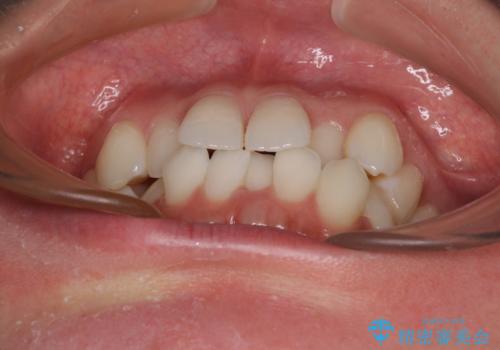

ワーキングホリデー前にきれいな歯列に

- 2、3年後にワーキングホリデーで海外に行くため、その前に歯列やむし歯をきれいにしたいとのことで来院された患者様です。

抜歯の必要な右上の奥歯は事前に抜歯をし、インビザラインにて上下歯列を整えることとしました。

矯正治療後半に奥歯の補綴治療が必要な歯にはオールセラミッククラウンを装着し、インビザラインで最終的に仕上げることとしました。